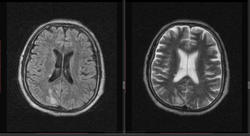

Мужчина 1964 г.р. Жалобы на нарушение памяти, снижение зрения и кратковременную потерю сознания, температура нормальная.

Я думаю что это может быть какой нибудь васкулит, либо Posterior Reversible Encephalopathy Syndrome, о чем можно думать в данном случае?

Контраста нет. Дайком тут!

eto pres

Я представлял синдром с более выраженным изменением сигнала от белого вещества и меньшим - коры.